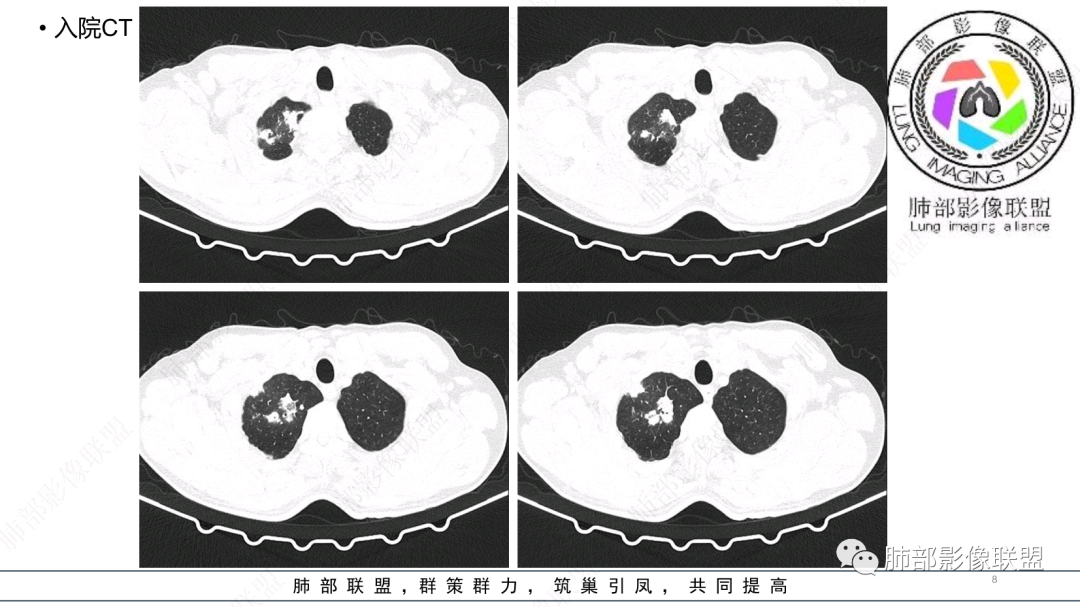

中老年男性,发病一周,发热,炎症指标明显增高,双肺支气管扩张基础,双肺可见多发结节、斑片状、团块状密度增高,边缘尚清。病灶分布与支气管关系密切,考虑支扩合并感染,铜绿,NTM、奴卡、曲霉等,环卫工人,可能接触腐败物较多,考虑曲霉可能大,鉴别奴卡。

男性,56岁,清洁工,临床表现咳嗽咳痰发热。胸部影像:两肺散在斑片、结节及实变影,大部分沿气道分布,以下肺为著并伴发多发支气管扩张及囊腔影,实验室检查白细胞增高,考虑感染性病变,曲霉、铜绿及NTM。

56岁,工作性质:环卫工人。主诉:咳、痰、喘、发病一周。急性起病(或者慢病+AE),呼吸道感染症状。化验指标白细胞、中性、CRP明显升高。影像学显示多灶性,有柱状支扩,囊状支扩等结构肺病,责任细菌主要考虑铜绿假单胞菌,不排除合并其他细菌以阴杆为主;存在树芽影,发热,炎症沿支气管束分布,是否合并TB?真菌?;树芽伴发热支原体感染也要需要考虑进去;全肺多灶性炎症,部分病灶周围有晕,右上叶疑似反晕,内部疑似有丝,右下肺考虑存在粘液栓,加之环卫工工作性质,考虑霉菌,主要考虑曲霉。

CT:双肺延支气管血管束分布斑片状、团块状、树芽状密度增高影,部分边界模糊,支气管扩张、部分管壁增厚。考虑气道吸入细菌性感染,铜绿假单孢?